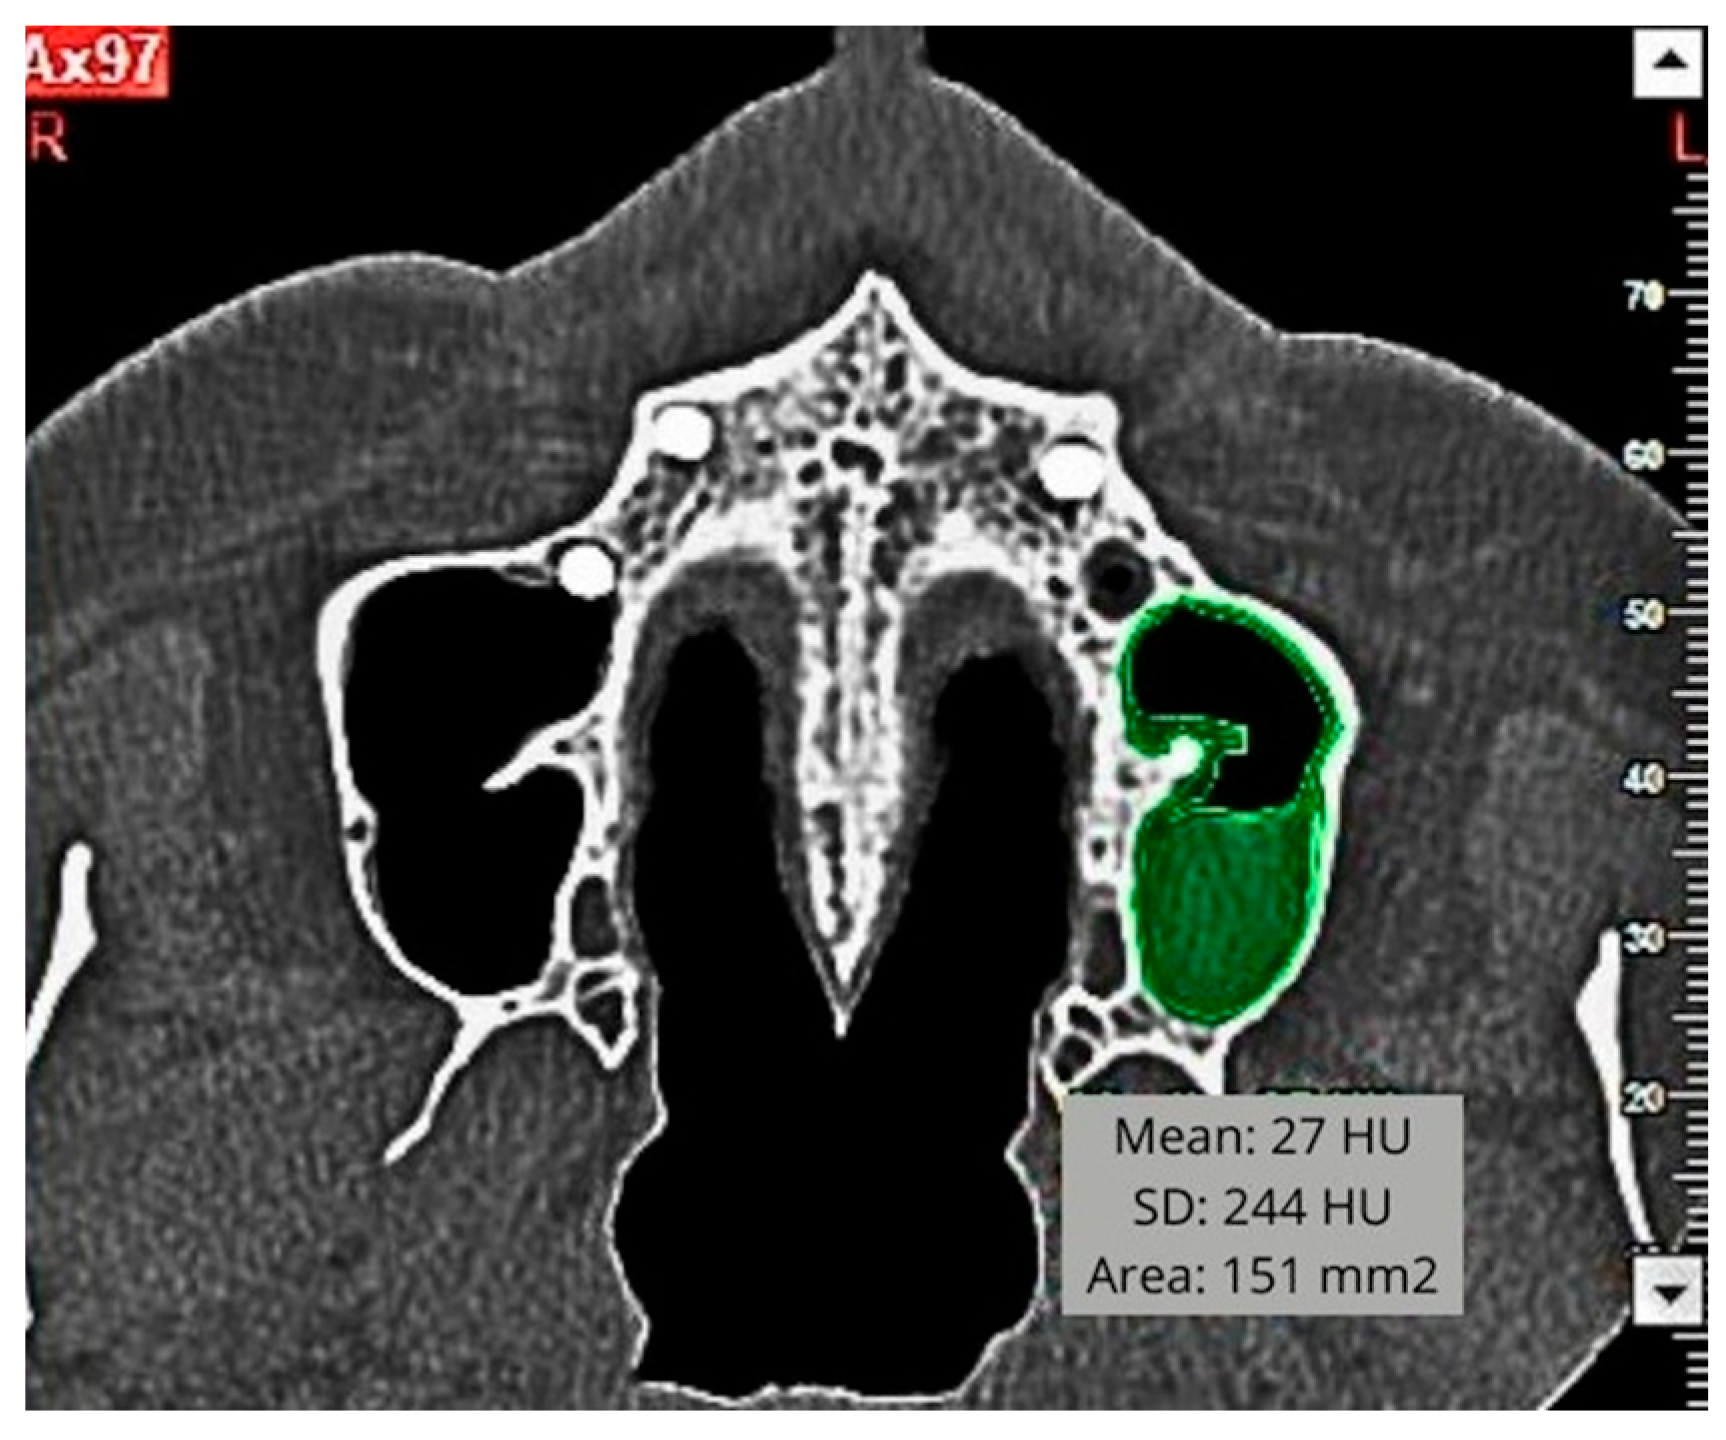

2.5. Morphometric Measurements

| Patient | SMT Pattern | SMT Area (mm2) | SMT Density (HU) | SMT Max Height (mm) T1-T0 | |||||

|---|---|---|---|---|---|---|---|---|---|

| Pn | Ort | Ax | Pn | Ort | Ax | Pn | Ort | ||

| 1 | C | 221.94 | 153.36 | 280.98 | 242.4 | 63.4 | 287.1 | 17.1 | 16.7 |

| 2 | C | 160.9 | 118.26 | 141.03 | 74.2 | 306.8 | 461.3 | 11.9 | 13.1 |

| 3 | C | 117.45 | 57.15 | 172.8 | 261.8 | 353.9 | 558.6 | 3.1 | 2.1 |

| 4 | H | 201.33 | 50.4 | 191.43 | 119.2 | 343.3 | 205.1 | 11.2 | 2.7 |

| 5 | C | 348.39 | 119.07 | 209.61 | 165.3 | 81.2 | 307.5 | 19.2 | 11.7 |

| 6 | H | 321.66 | 129.42 | 236.52 | 86.1 | 35.8 | 247.1 | 11.4 | 9.2 |

| 7 | H | 114.12 | 70.74 | 111.78 | 152.2 | 430.8 | 256.3 | 17.7 | 6.0 |

| 8 | C | 289.35 | 207.9 | 364.32 | 196.5 | 107.7 | 165.0 | 19.7 | 19.5 |

| 9 | C | 506.34 | 153.09 | 310.14 | 166.3 | 113.2 | 197.4 | 18.0 | 14.9 |

| 10 | C | 116.73 | 72.75 | 109.53 | 145.0 | 108.3 | 365.9 | 15.9 | 2.3 |

| 11 | C | 411.12 | 209.88 | 317.16 | 128.0 | 91.4 | 219.4 | 21.3 | 23.6 |

| 12 | C | 169.11 | 96.39 | 99.36 | 23.7 | 179.5 | 480.0 | 16.7 | 3.6 |

| 13 | C | 112.32 | 58.95 | 82.26 | 96.1 | 41.8 | 247.3 | 2.4 | 3.0 |

| 14 | H | 199.89 | 111.33 | 404.37 | 21.8 | 186.6 | 343.3 | 9.9 | 13.2 |

| 15 | C | 234.54 | 85.5 | 269.73 | 71.2 | 428.5 | 178.8 | 9.3 | 9.8 |

| 16 | C | 78.84 | 17.55 | 60.12 | 366.2 | 404.8 | 271.0 | 4.2 | 2.8 |

| 17 | C | 219.24 | 105.39 | 189.63 | 179.9 | 703.4 | 327.3 | 8.1 | 4.5 |

| 18 | C | 173.52 | 97.74 | 233.73 | 248.2 | 188.7 | 320.5 | 5.1 | 12.4 |

| 19 | H | 136.26 | 36.63 | 120.87 | 72.5 | 218.4 | 584.0 | 3.0 | 3.2 |

| 20 | C | 223.74 | 154.71 | 290.88 | 335.7 | 115.5 | 395.6 | 3.7 | 10.5 |

| 21 | H | 238.32 | 83.97 | 89.73 | 295.1 | 278.1 | 582.0 | 4.5 | 3.4 |